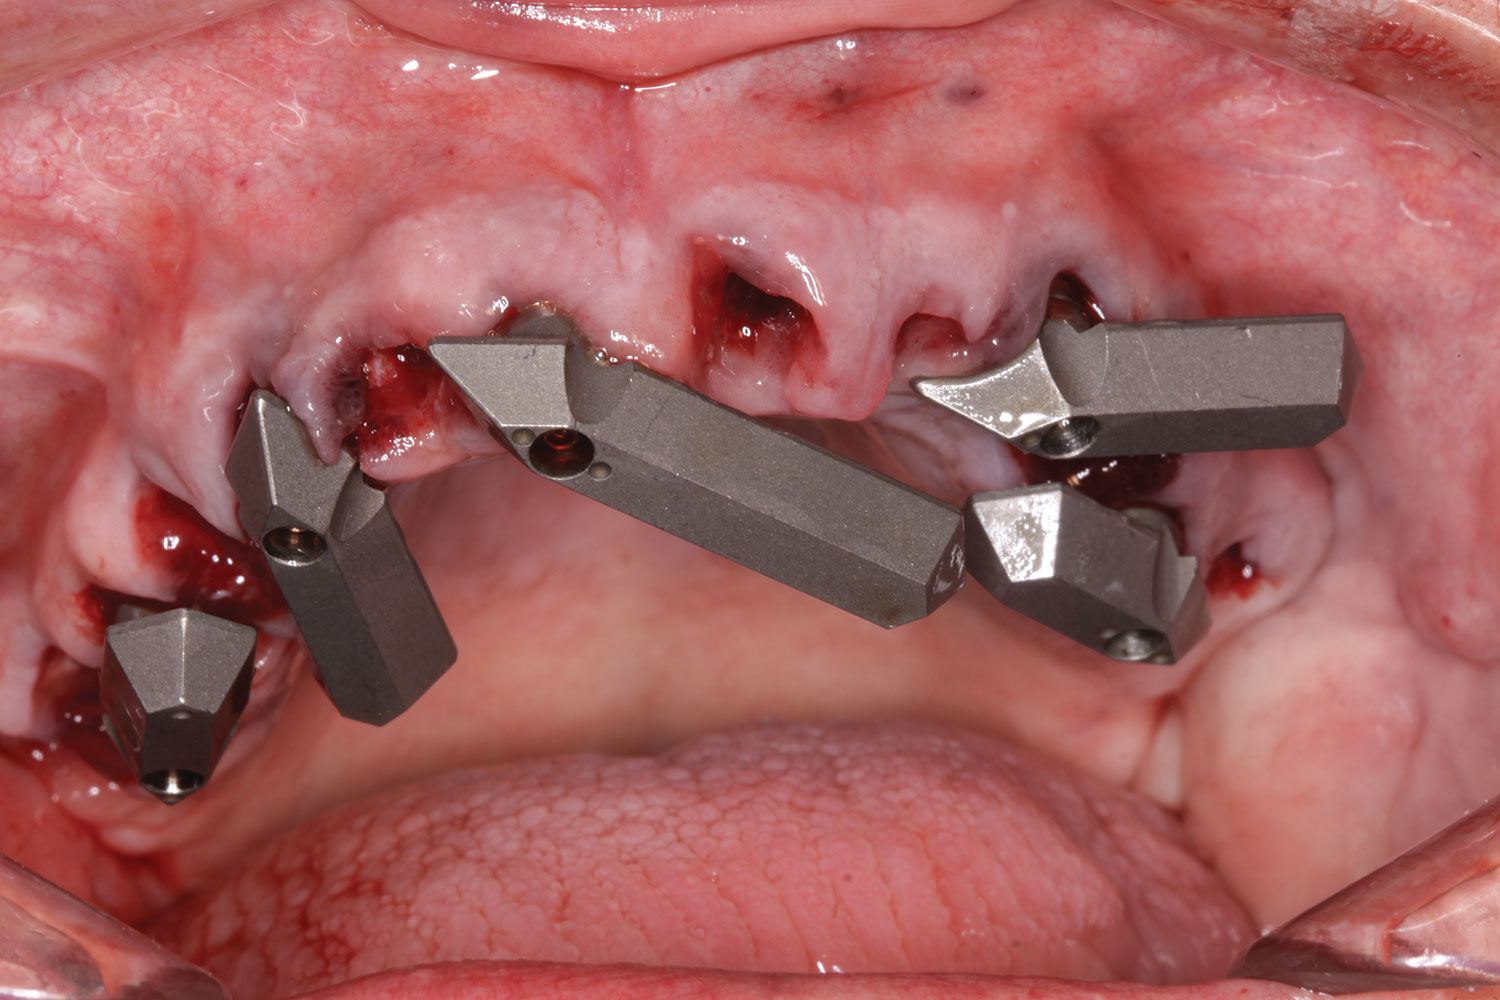

A week later the patient presented for surgery for extraction and replacement of her existing maxillary dentition with implants and a screw-retained provisional implant restoration. Teeth Nos. 2, 4, and 6 through 11, 13, and 14 were carefully extracted with attention paid to retaining site dimensions. Immediate implants were inserted into sites Nos. 4, 6, 8, 11, and 13 with high insertion torques in excess of

40 Ncm. Subsequently, multi-unit abutments were placed on all the implants and torqued to 30 Ncm, and scan gauges were placed on implant Nos. 8 and 11 (Figure 12 and Figure 13).

A maxillary intraoral scan was obtained with a digital scanner capturing the two remaining teeth in sites Nos. 5 and 12 and the scan gauges on implants Nos. 8 and 11. Subsequently, teeth Nos. 5 and 12 were extracted. Scan gauges were placed on implants Nos. 4, 6, and 13. At this time, another intraoral scan was captured of all the scan gauges on the five implants with the surrounding soft tissues (Figure 14 and Figure 15).

Fig 14. All implants, multi-unit abutments, and scan gauges in place.

Figure 14

Fig 15. Completion of maxillary flapless immediate implant surgery and placement of multi-unit abutments.

Figure 15